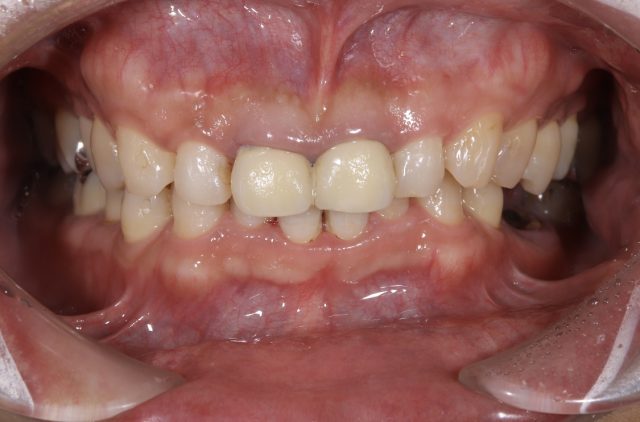

| 診断名 | セラミックインレー審美補綴治療 |

|---|---|

| 年齢・性別 | 50代・女性 |

| 治療期間・回数 | 2週間~3週間/2回 |

| 治療方法 | セラミックインレーによる審美補綴治療 |

| 費用 | 55,000円(税込み) |

| デメリット・注意点 | 保険が適用できないため自費診療になる。 セラミックスインレー・クラウンに強い力がかかると割れてしまう恐れがあるため、歯ぎしりや食いしばりが癖になっている患者様にはおすすめできない場合がある。 |